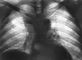

Диагноз устанавливают на основании клинической картины (подозрение на лимфогранулематоз могут вызвать такие симптомы, как стойкое увеличение периферических лимфатических узлов, жалобы на ночные боли в области поясницы, кожный зуд, немотивированные подъемы температуры тела, сопровождающиеся слабостью, потливостью) и результатов инструментального и лабораторного исследований. Большое значение в диагностике лимфогранулематоза, особенно на ранних этапах заболевания, имеет рентгенологическое исследование органов грудной клетки, и в частности лимфатических узлов средостения. При поражении лимфатических узлов переднего средостения на рентгенограммах, выполненных в прямой проекции, отмечается двустороннее, реже одностороннее, расширение верхних (реже средних и нижних) отделов срединной тени, которая имеет полициклические контуры и четкие (при отсутствии прорастания легочной ткани) очертания (рис. 4). На рентгенограммах в боковой проекции определяется затемнение переднего средостения. При поражении лимфатических узлов средостения, располагающихся непосредственно вблизи крупных сосудов, наблюдается асимметричное расширение срединной тени, чаще в области дуги аорты или легочного ствола. Иногда отмечается увеличение внутригрудных, чаще бронхопульмональных лимфатических узлов.

Поражение легочной ткани при лимфогранулематозе, в большинстве случаев обусловленное переходом процесса с лимфатических узлов средостения и внутригрудных лимфатических узлов, проявляется грубой тяжистостью рисунка, распространяющейся от срединной тени к периферии; на этом фоне в результате прогрессирования процесса появляются инфильтраты. При самостоятельном лимфогранулематозном поражении легочной ткани на рентгенограммах видны очаговые тени, изолированные инфильтраты и опухолевые узлы. При распаде легочной ткани рентгенологическая картина полиморфна; чаще определяются небольшие полости неправильной формы.